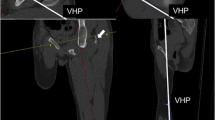

3D images of bilateral lower limb long bones, including the femur, tibia, fibula, and first metatarsus, were virtually reconstructed on the automated CT image analyzing system Volume Analyzer SYNAPSE VINCENT version 3 (FUJIFILM Medical Co., Ltd., Tokyo), identifying each bone shape based on the manufacturer’s graph-cut algorithm, which automatically estimates the CT value distribution and optimal boundary for region segmentation of the bones without users’ intervention [23, 34, 35]. The first metatarsus was chosen because it is a well-preserved foot bone in decomposed bodies and easy to identify when recovered separately [36]. Measured parameters were bone mass volume (cm3), maximum (max.) length (mm) (vertical distance between proximal and distal endpoints) (Supplementary Fig. S1), and the mean CT attenuation (HU) value and total CT attenuation (HU) value (mean HU × bone volume). The mean CT attenuation (HU) value was automatically provided for the whole extracted bone. Manual 3D measurement of the bone length was performed by three independent observers, and intraobserver and interobserver precisions were examined by applying three widely used precision estimates: the technical error of measurement (TEM), the relative technical error of measurement (rTEM), and the coefficient of reliability (R) [16]. Virtual measurements of the maximum bone length were compared with the manual measurements using skeletonized dry bone samples of the femur, tibia, and fibula (n = 7 for each) to examine the reliability. These measurements were repeated two times for each bone.

3D images of individual bones were virtually reconstructed on the automated CT image analyzing system two times in all cases. The reproducibilities of the extracted bone volume and CT density were 100.0 %. In manual measurements of bone lengths, intraobserver precisions were TEM = 0.149–1.316, rTEM < 1.5 %, and R > 0.95; interobserver precisions were TEM = 0.752–1.878, rTEM < 2.0 %, and R > 0.95 (Table 1). The differences between the virtual measurements using the volume analyzer and manual measurements of skeletonized dry bone samples of the femur, tibia, and fibula were 0–2 mm (errors within 0.005 % for each bone length).

The correlations between max. bone lengths and the stature were positive and significant in all cases (r = 0.42–0.85, SEE = 4.81–8.57 cm, p < 0.0001), and also in males (r = 0.33–0.74, SEE = 4.72–6.49 cm, p < 0.0001) and females (r = 0.55–0.85, SEE = 4.17–6.64 cm, p < 0.0001); however, lower correlations with greater SEE were detected for the first metatarsus (r = 0.33–0.68, SEE = 5.79–8.57 cm, p < 0.0001) than for the other bones (r = 0.71–0.85, SEE = 4.17–5.35 cm, p < 0.0001) (Table 3 and Supplementary Fig. S2). Bone mass volumes showed correlations with the statures in all cases, and in males and females (r = 0.58–0.83, SEE = 4.93–6.15 cm, p < 0.0001); the correlation of the first metatarsus (r = 0.58–0 77, SEE = 5.70–6.15 cm, p < 0.0001) was higher than that for the length (Table 3 and Supplementary Fig. S2). Mean HU value showed an age-dependent decrease in all cases, and in males and females (r = −0.30 to −0.83, p = 0.0002 for male right femur and p < 0.0001 for the others), showing significant difference between females of <60 and >60 years of age (p < 0.0001, Fig. 1); however, total CT attenuation value (HU) correlated with the stature in all cases, and in males and females (r = 0.62–0.82, SEE = 5.02–6.04 cm, p < 0.0001) (Table 3 and Supplementary Fig. S2). There was a substantial right-left difference in max. length of the first metatarsus (r = 0.69, p < 0.0001); however, such bilateral asymmetry was not significant for the first metatarsal volume and each parameter of the other bones (r = 0.92–0.99, p < 0.0001). As above, correlations with the stature were similar for the lengths and mass volumes of the femur, tibia, and fibula but were higher for the mass volume of the first metatarsus without bilateral asymmetry, showing regression equations for stature estimation using bilateral data: 30.037 + (0.309 * max. femur length); 40.638 + (0.361 * max. tibia length); 36.392 + (0.368 * max. fibula length); and 123.607 + (2.151 * first metatarsal volume). When the sampling error was examined by random resampling and recalculation, reducing sample numbers to 100 and 50, the correlations between the stature and individual parameters (r values) did not show significant difference (<0.05).